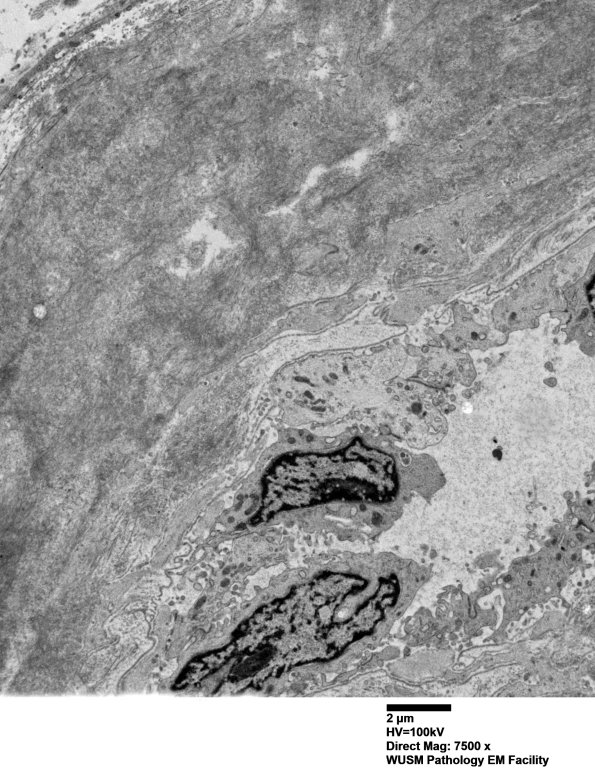

This endoneurial venule has an expanded wall which consists of aggregates of fibrils. (electron micrographs)